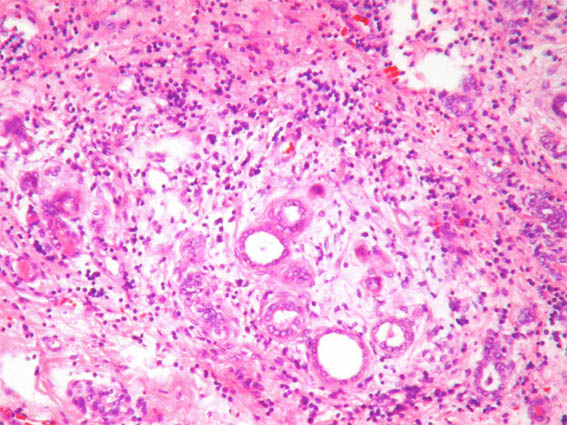

In a 44-year-old woman was incidentally detected, by ultrasound, a renal mass of 3.0 cm of diameter in the upper pole of the left kidney. She had cholelithiasis, with no other clinical alterations. Renal function tests and urinalysis were normal.

Nephrectomy was performed. We receive the case in consultation. See the images:

Figure 5. H&E, X200.